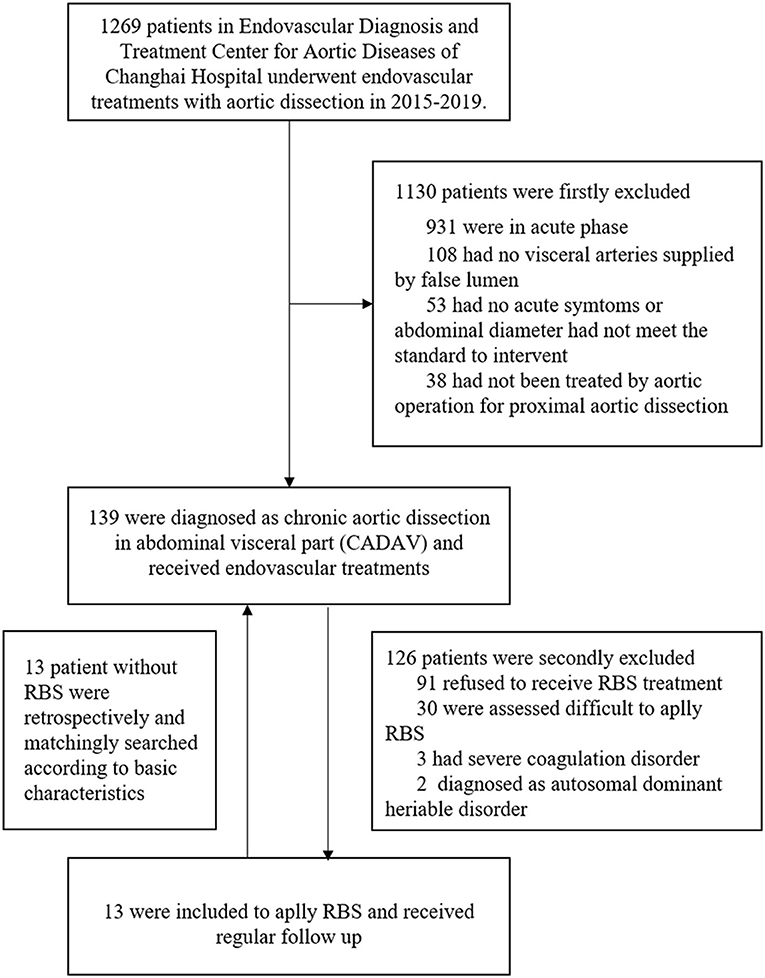

The exclusion criteria consisted of (1) Patients that refused to receive RBS procedure; (2) Patients that assessed difficult to apply RBS, such as distal tears were excluded or too small to let guidewire pass through; (3) Presence of any coagulation disorder, such as severe thrombocytopenia or hemophilia; (4) Patients diagnosed with autosomal dominant heriable disorder, such as Marfan syndrome. After inclusion and exclusion, 13 patients finally included to apply RBS. According to their basic characteristics, anatomical features and previous solutions of aortic dissection, another 13 patients without RBS were retrospectively matched for comparation (Figure 1).

A total of 139 patients were diagnosed with chronic aortic dissection involving visceral arteries at our center from January 2015 to December 2019. A total of 126 patients were excluded for the following reasons: 91 refused to receive RBS treatment, 30 were assessed difficult to apply RBS, 3 had severe coagulation disorder, 2 diagnosed as autosomal dominant heritable disorder. In order to compare the effectiveness of RBS, we retrospectively selected 1:1 paired matched patients (n = 13) who had not underwent RBS and followed up regularly in the 126 excluded patients. Finally, a total of 13 patients suffering from distal dilatation of CADAV who underwent RBS and followed up regularly were included in the present analysis.